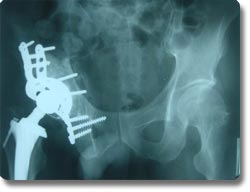

关节置换可以说是本世纪骨科手术最伟大的突破之一。目前它已应用於治疗肩关节、肘关节.腕关节、指间关节 、髋关节、膝关节及踝关节等疾患,但以全人工髋关节及膝关节置换最为普遍。对骨关节炎、股骨头无菌性坏死、老年性股骨颈骨折等疾病具有明显治疗效果,我科目前已开展各种置换手术800余例,疗效受到患者普遍肯定。 |